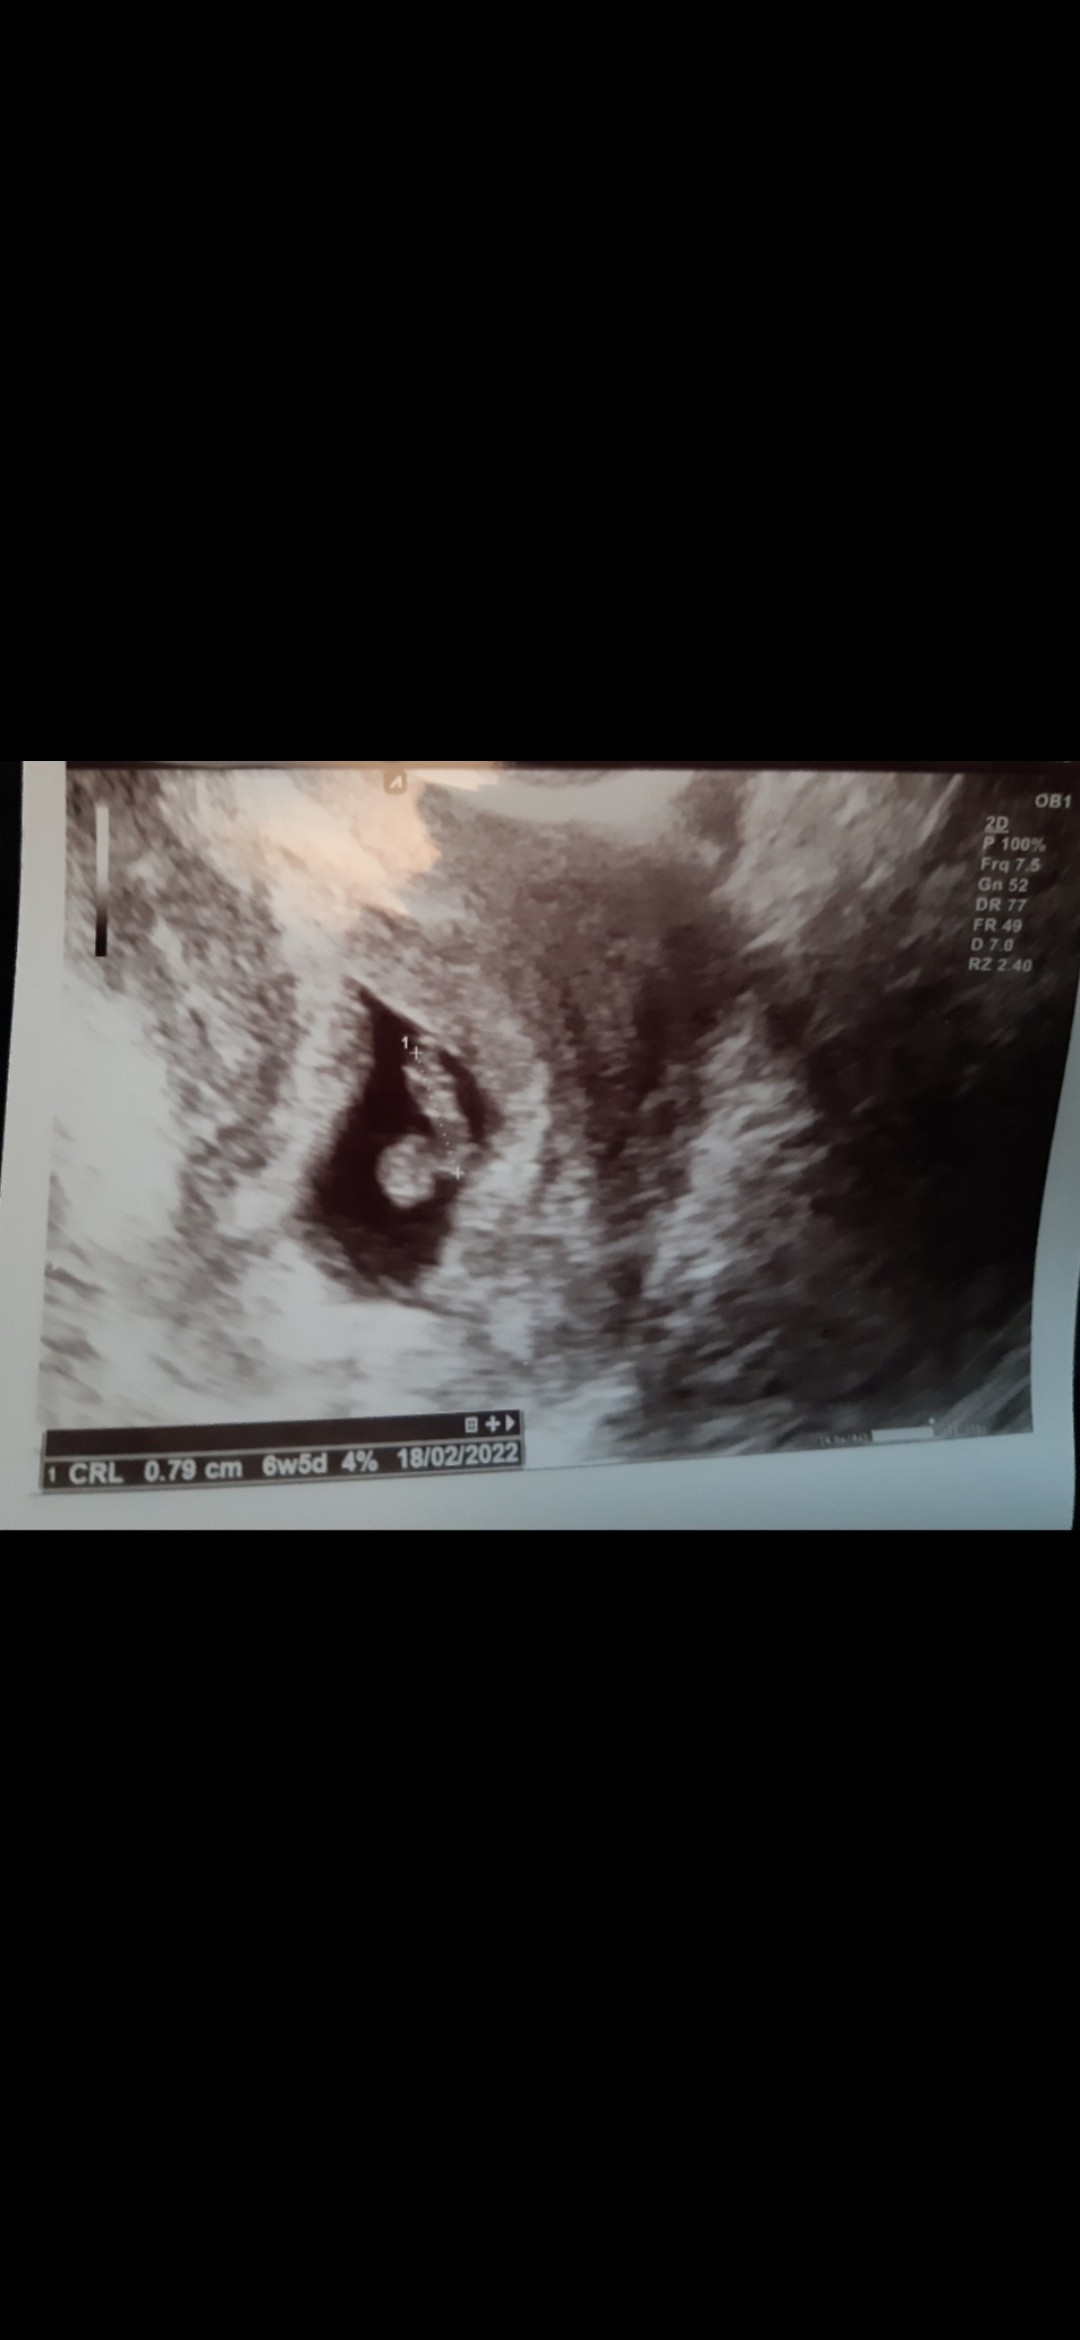

Czesc jestem w 6tc i po ostatniej wizycie pani doktor która najpierw mnie skomentowała ze w krótkich spodenkach się nie przychodzi do lekarza bo ona czuje się obrazona pierwszy raz się z czym takim spotkalam zdenerwowana przebadała mnie i mówi ze tu coś jest nie tak bo nie ma serca ani głowy ze chyba bezczaszkowiec I ona się pod tym nie podpisze i dala mi skierowanie do szpitala na szczegółowe badanie USG ( na skierowaniu napisala niewyraźny obraz usg chyba ciąża obumarla)Poszlam ale p.doktor powiedzial ze dopiero za tydzień możemy zobaczyć czy wszystko ok bo to wczesna ciąża.Chce jeszcze dodać ze tydzień temu bylam prywatnie i lekarz na usg powiedział ze widzi sam pęcherzyk.Co Wy o tym myślicie i uważacie bo jestem bardzo zdenerwowana szczegółowe badanie bede miec 4sierpnia.Jestem załamana.Ilona 40lat druga ciąża.

• 20210721_092425.jpg

20210721_092425.jpg

1,5 MB · Wyświetleń: 573

Niestety we wcześniejszej ciąży miałam puste jajo płodowe takie zdjęcie jak Ty wyżej i lekarz też powiedział w prost że nic z tego nie będzie tylko trzeba czekać na poronienie i w między czasie sprawdzać przyrost bety w 8/9 tc zaczęła spadać . Ale za Ciebie trzymam kciuki i mam nadzieję że rośnie t mały człowiek :)